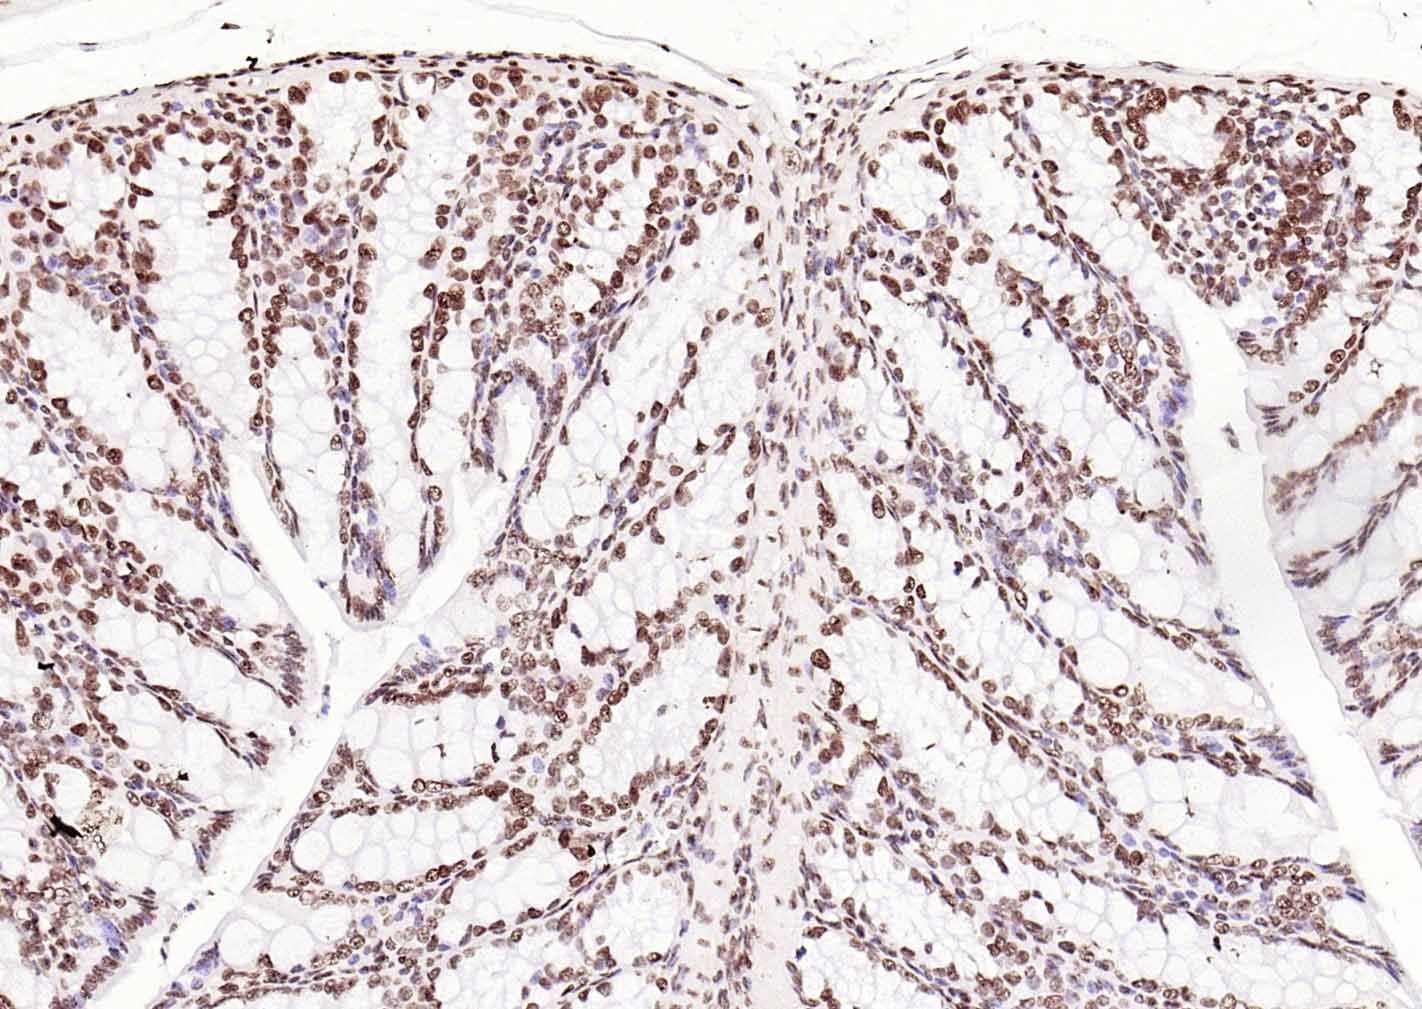

Paraformaldehyde-fixed, paraffin embedded (human breast carcinoma); Antigen retrieval by boiling in sodium citrate buffer (pH6.0) for 15min; Block endogenous peroxidase by 3% hydrogen peroxide for 20 minutes; Blocking buffer (normal goat serum) at 37°C for 30min; Incubation with (ERCC1 ) Monoclonal Antibody, Unconjugated (bsm-60230R) at 1:500 overnight at 4°C, followed by operating according to SP Kit(Rabbit) (sp-0023)instructionsand DAB staining.